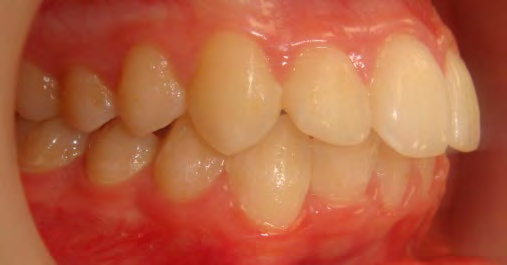

All of the patients below had been told they required extractions by orthodontists, some insisting that they could not be treated without extractions.

They were all treated without extractions, head gear or facemasks at Vakresmil and represent just a small sample of cases treated between 2004–2014.

The patient below had severe crowding of both upper canines and the lower right 5. The upper 4’s and 2’s were actually in contact.